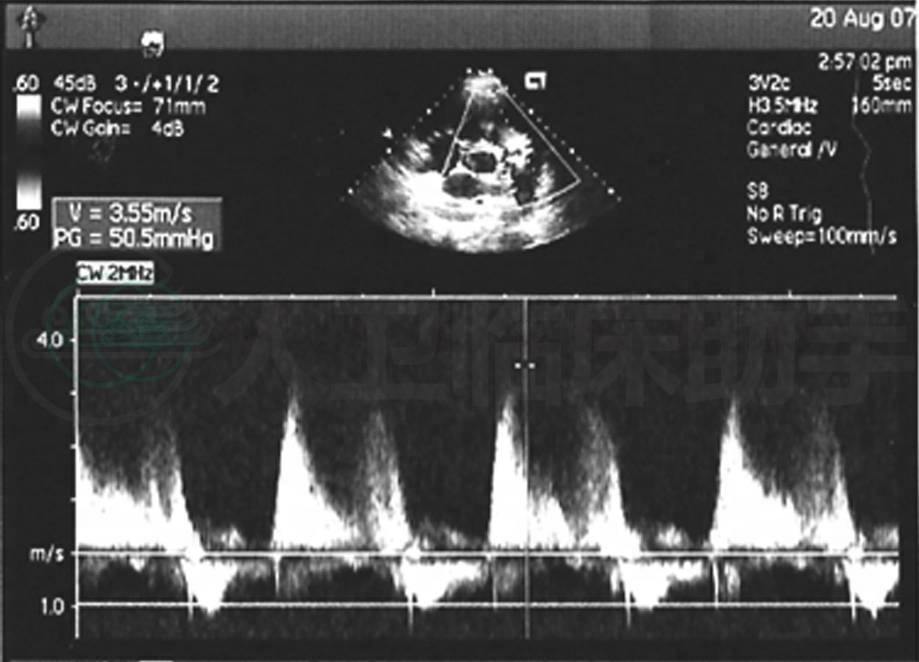

入院前门诊超声心动图(图3):左心室舒张末期前后径36mm,射血分数78%,右心室前后径40mm,右心房、右心室扩大,右心室壁增厚,运动正常,左心室内径大致正常。室间隔左移,左心室呈“D”字形,房、室间隔完整。室壁厚度正常,室间隔运动异常。肺动脉明显扩张,腔内未见明显异常回声。三尖瓣环扩张,致瓣叶对合不拢。余瓣膜形态、结构启闭未见明显异常。三尖瓣少量高速反流,肺动脉瓣少~中量高速反流,估测肺动脉收缩压84mmHg。

图3 入院前门诊超声心动图:右心扩大,肺动脉高压